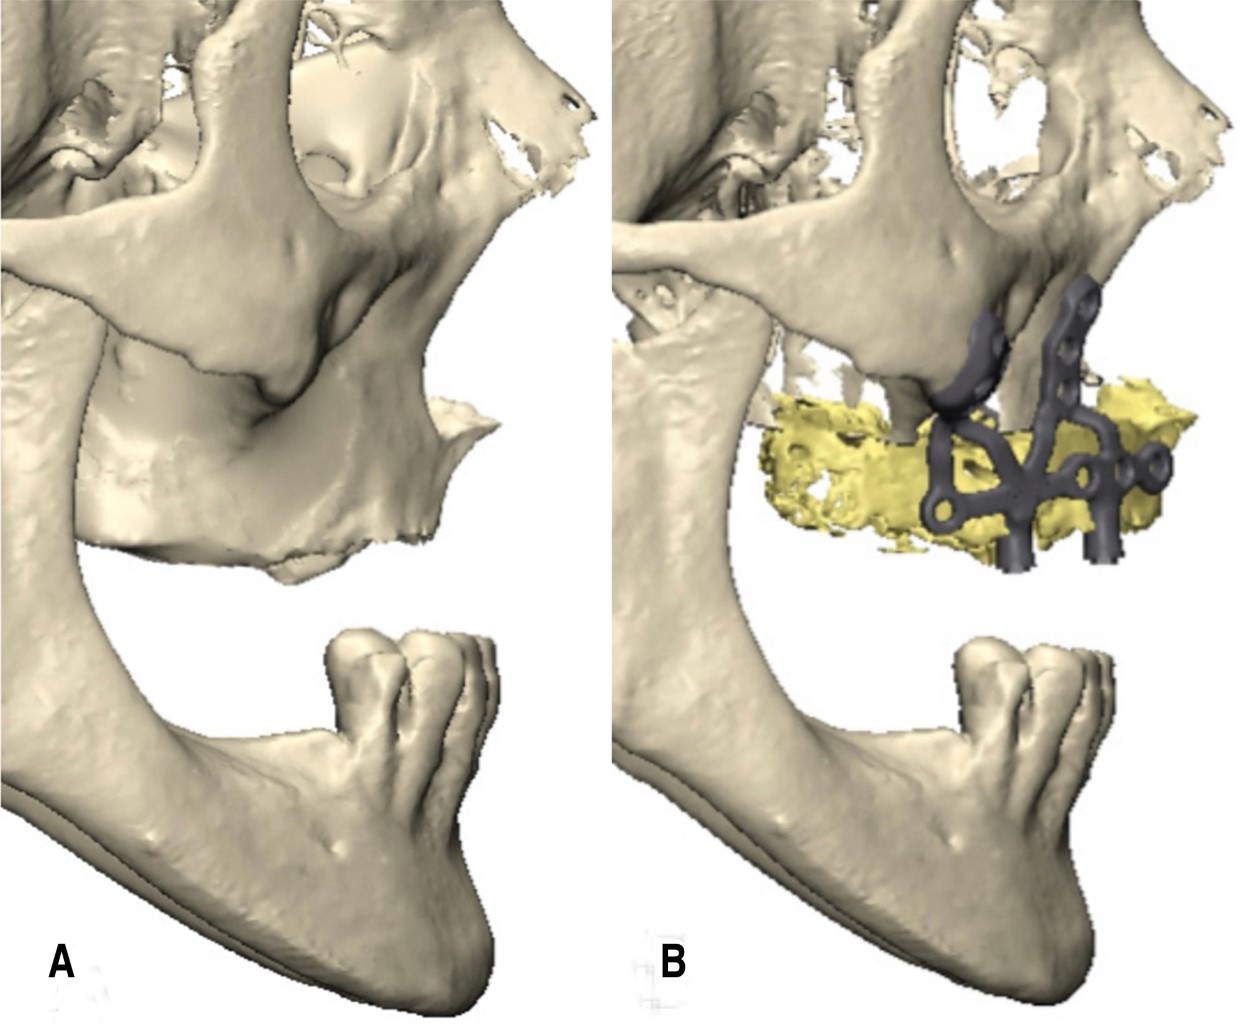

Para los casos resueltos por nosotros, la reconstrucción 3D de la tomografía, la planificación y el diseño de las guías e implantes, fueron realizados con el paquete de software Mimics Innovation Suite (Materialise, Bélgica).

La fabricación del implante subperióstico personalizado y de las guías quirúrgicas asociadas fue realizada en aleación de titanio grado 23 (Ti-6Al-4V ELI) mediante manufactura aditiva con tecnología láser. La impresora utilizada fue una Renishaw modelo AM400; las estructuras se fabricaron en capas de 40 micrones de espesor (RAOMED, Córdoba, Argentina). Después de la fabricación, las piezas fueron sometidas a un tratamiento térmico durante 20 horas; posteriormente recibieron procesos de desbaste y terminación, y finalmente fueron lavadas y esterilizadas. El implante subperióstico personalizado diseñado mediante este proceso fue el utilizado en el caso clínico que se presenta a continuación.

El caso que se ilustra presenta la necesidad de avanzar el maxilar para compensar la discrepancia sagital y, además, dificultad para colocar implantes cigomáticos por tener poco espacio y anatomía desfavorable del hueso malar, muy delgado y de gran concavidad respecto a la delgada cresta residual. Se realizaron guías de perforación, osteotomía y fresado. Los implantes yuxtaóseos se diseñaron de manera tal que combinan osteosíntesis del avance maxilar y portadores de los pilares protésicos para la reconstrucción dentomaxilar.

Se decidió un abordaje combinado con osteotomía tipo Le Fort I, con avance maxilar de 10 mm, y colocación de implantes yuxtaóseos personalizados, planificados digitalmente con base en la anatomía remanente. Esta decisión quirúrgica se justificó por la precariedad volumétrica de los huesos malares, que impedía el anclaje bicortical cigomático, sumado a la contraindicación por patología sinusal crónica (Figuras 4, 5, 6 y 7). El procedimiento fue realizado bajo anestesia general, sin complicaciones, utilizando guías quirúrgicas. La cirugía concluyó con procedimiento complementario de ritidectomía (Figura 8).